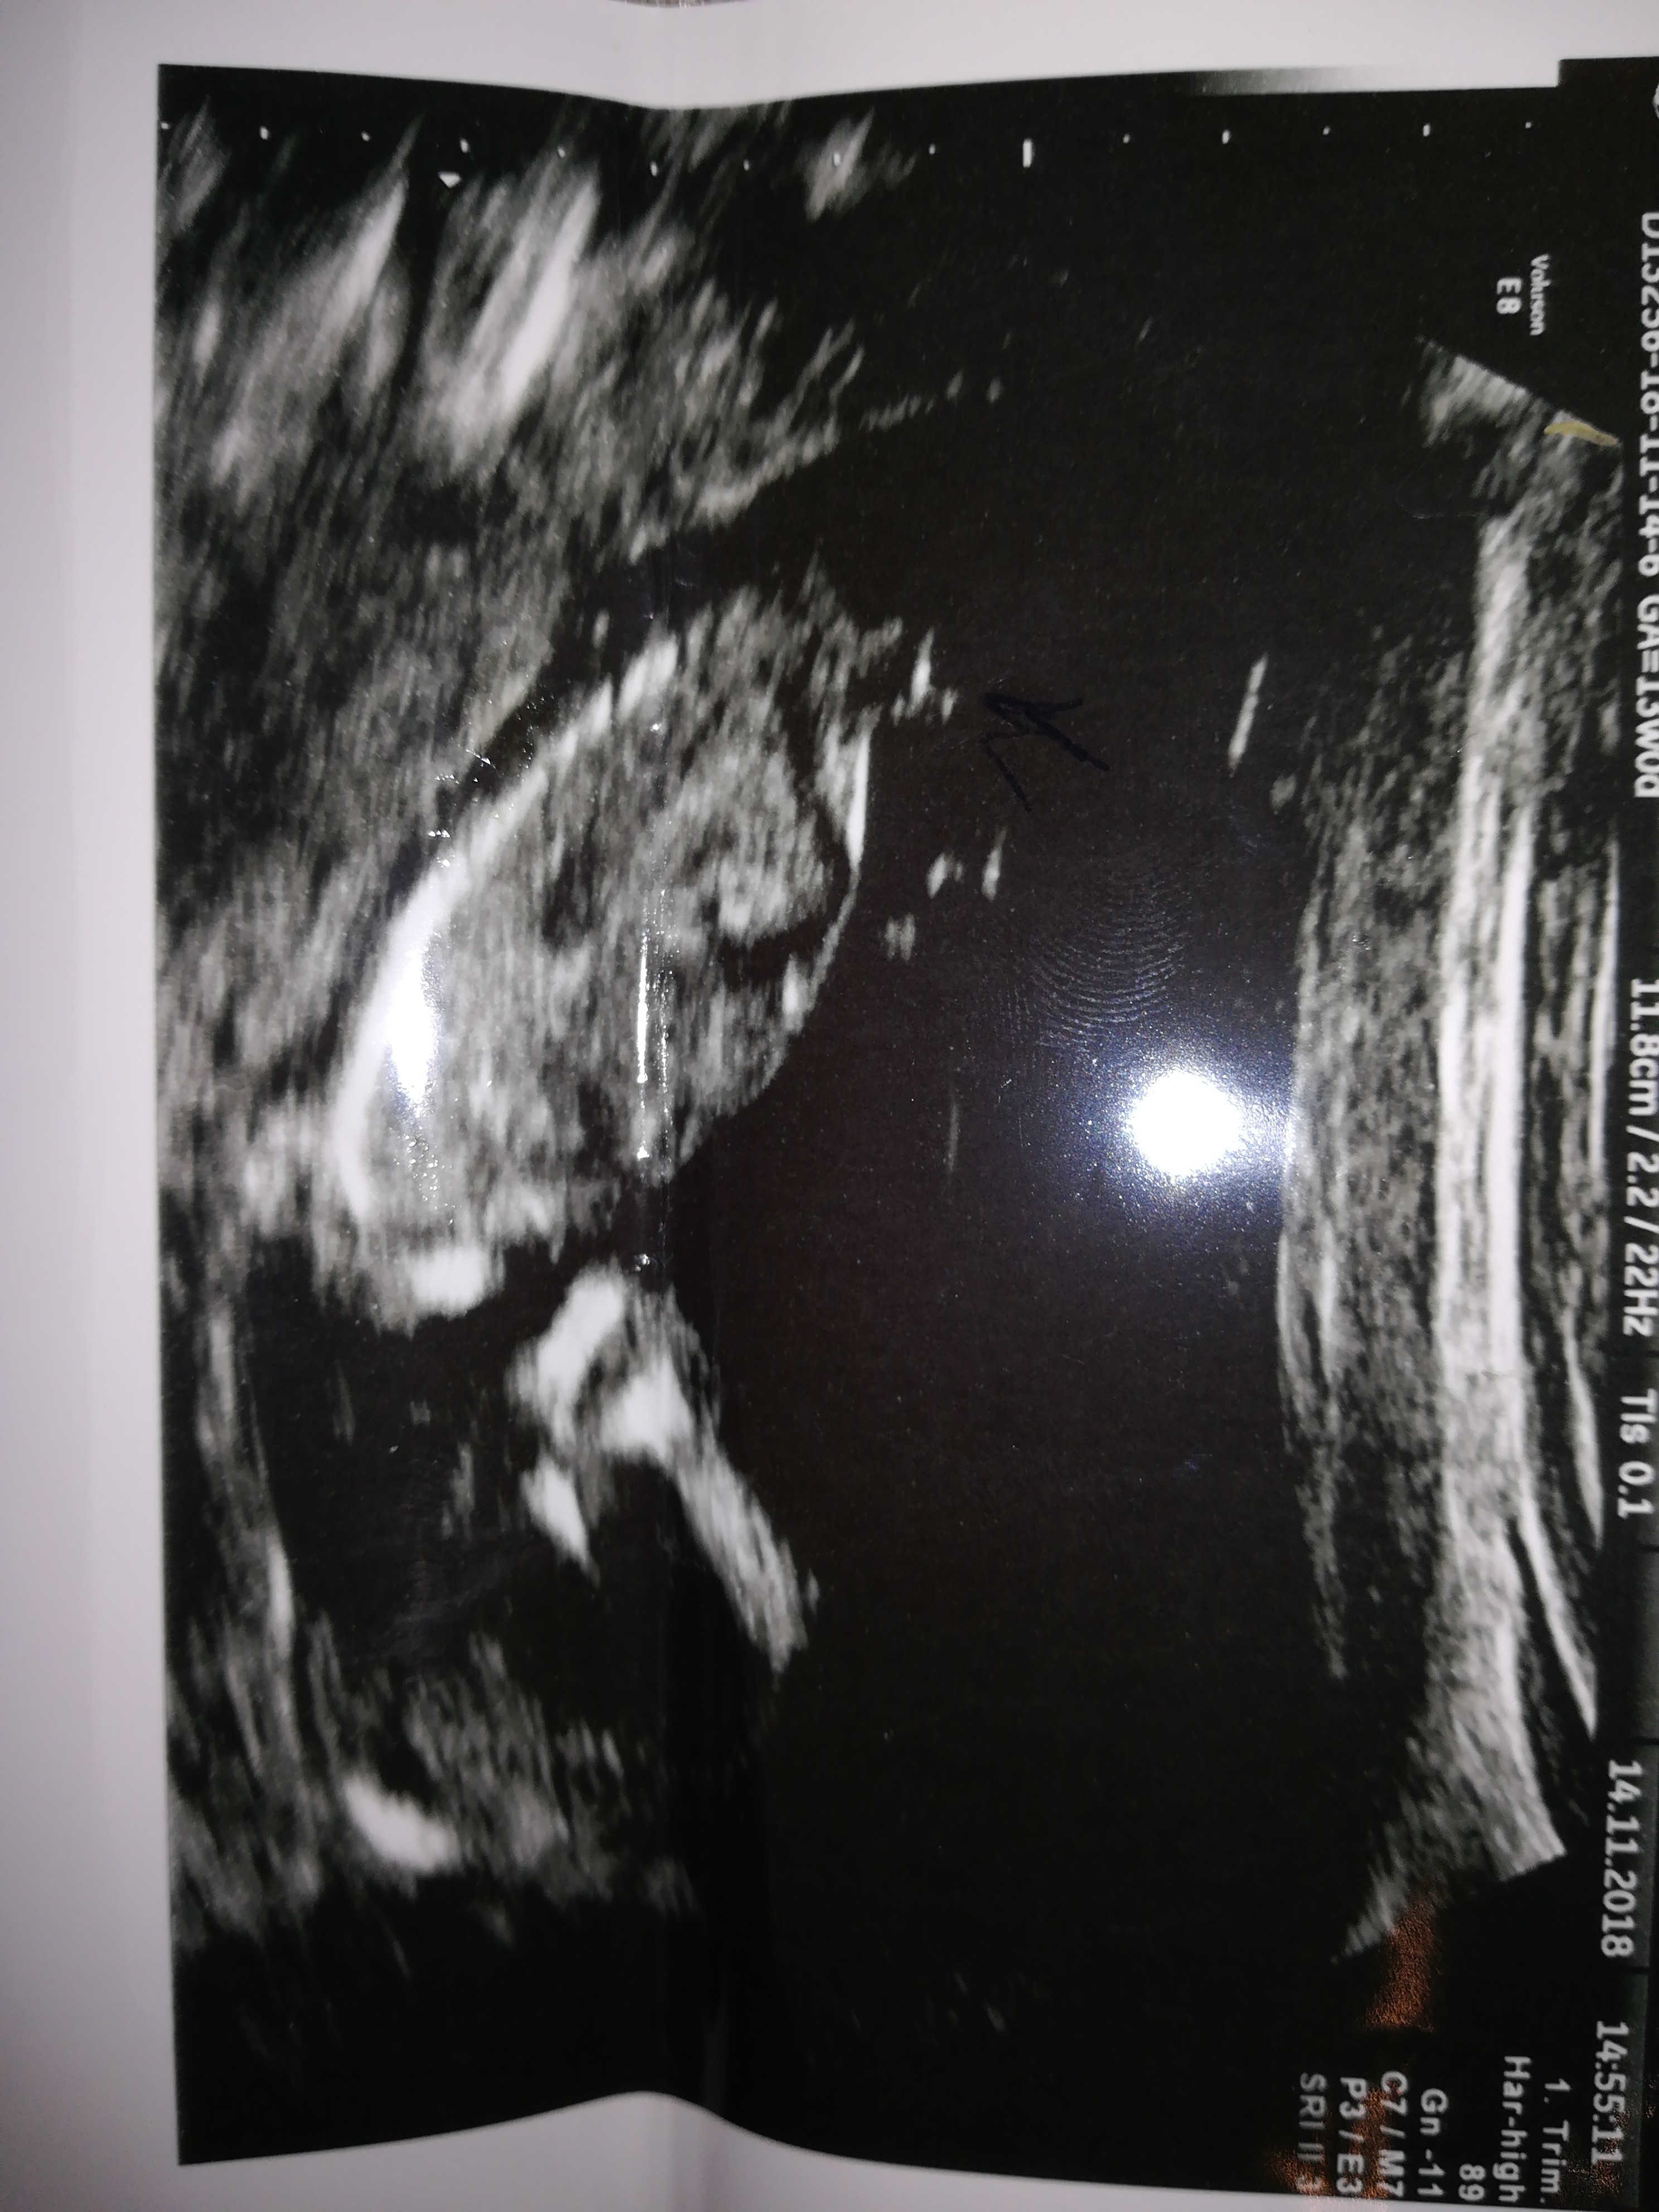

Witam w 19 tygodniu ciąży dowiedziałam się ze będę miała dziewczynkę w 20 tyg okazało się jednak , że to chłopak. Sama już nie wiem bo na jednym usg widać na pewno dziewuche a na drugim chłopca. Może to pempowina ?? Może ktoś mi pomoże rozwiązać ta zagadkę

Jestem po usg genetycznym 13 tydzień pani doktor twierdzi że chłopak. Myślicie że się nie myli?

Maziajka może teraz coś lepiej widać? Doktor zaznaczyła strzałka niby siusiaka.